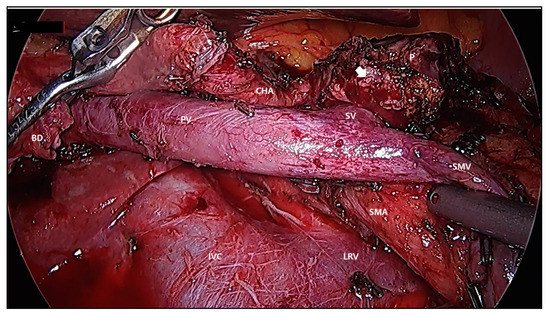

- Rho, S.Y.; Kim, J.S.; Chong, J.U.; Hwang, H.K.; Yoon, D.S.; Lee, W.J.; Kang, C.M. Indocyanine Green Perfusion Imaging-Guided Laparoscopic Pancreaticoduodenectomy: Potential Application in Retroperitoneal Margin Dissection. J. Gastrointest. Surg. 2018, 22, 1470–1474. [Google Scholar] [CrossRef]

- Nagakawa, Y.; Hosokawa, Y.; Sahara, Y.; Takishita, C.; Hijikata, Y.; Osakabe, H.; Nakajima, T.; Shirota, T.; Katsumata, K.; Nakamura, M.; et al. Approaching the superior mesenteric artery from the right side using the proximal-dorsal jejunal vein preisolation method during laparoscopic pancreaticoduodenectomy. Surg. Endosc. 2018, 32, 4044–4051. [Google Scholar] [CrossRef]

- Morales, E.; Zimmitti, G.; Codignola, C.; Manzoni, A.; Garatti, M.; Sega, V.; Rosso, E. Follow “the superior mesenteric artery”: Laparoscopic approach for total mesopancreas excision during pancreaticoduodenectomy. Surg. Endosc. 2019, 33, 4186–4191. [Google Scholar] [CrossRef]

- Zimmitti, G.; Manzoni, A.; Addeo, P.; Garatti, M.; Zaniboni, A.; Bachellier, P.; Rosso, E. Laparoscopic pancreatoduodenectomy with superior mesenteric artery-first approach and pancreatogastrostomy assisted by mini-laparotomy. Surg. Endosc. 2016, 30, 1670–1671. [Google Scholar] [CrossRef]

- Kuroki, T.; Tajima, Y.; Kitasato, A.; Adachi, T.; Kanematsu, T. Pancreas-hanging maneuver in laparoscopic pancreaticoduodenectomy: A new technique for the safe resection of the pancreas head. Surg. Endosc. 2010, 24, 1781–1783. [Google Scholar] [CrossRef] [PubMed][Green Version]